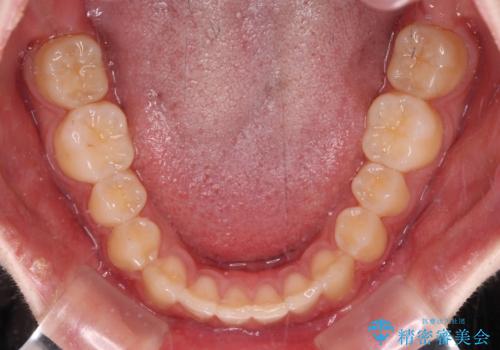

- 上顎前歯の隙間を気にして来院された患者様です。

目立たない装置を希望とのことで、インビザラインを用いて矯正治療を行うこととしました。

一度インビザラインのマウスピースセットをお渡しすると1年以上来院されず、マウスピースを破損したり紛失したりすると来院されるというのんびりとしたペースで治療を行ったため、4年間という長期にわたる治療となりました。

最終的には隙間は全て閉じ、綺麗な仕上がりとなりました。